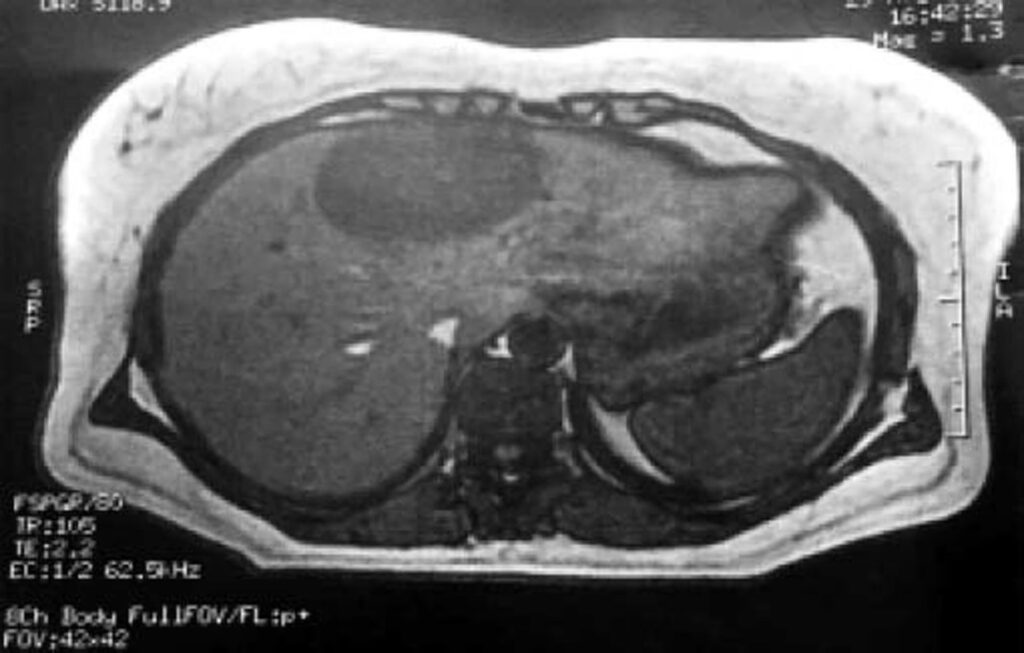

- Billeddiagnostik: Hverken ultralyd, CT- eller MR-scanninger kan med sikkerhed skelne et endometriom fra andre typer leverlæsioner som simple cyster, bylder (abscesser) eller endda levertumorer, både godartede og ondartede.

Den eneste måde at bekræfte diagnosen på er ved en histologisk undersøgelse, det vil sige en mikroskopisk analyse af en vævsprøve fra levermassen. At tage en biopsi af leveren før operation (transhepatisk biopsi) medfører dog risici, herunder blødning og spredning af celler, og er derfor ofte ikke den foretrukne metode. Derfor stilles den endelige diagnose ofte først efter, at massen er blevet fjernet kirurgisk. For at undgå unødigt store leveroperationer kan kirurger anvende en teknik kaldet intraoperativt frysesnit. Her tages en lille prøve under operationen, fryses hurtigt ned og undersøges af en patolog, mens patienten stadig er bedøvet. Dette kan give et hurtigt svar og hjælpe kirurgen med at beslutte omfanget af den nødvendige operation.